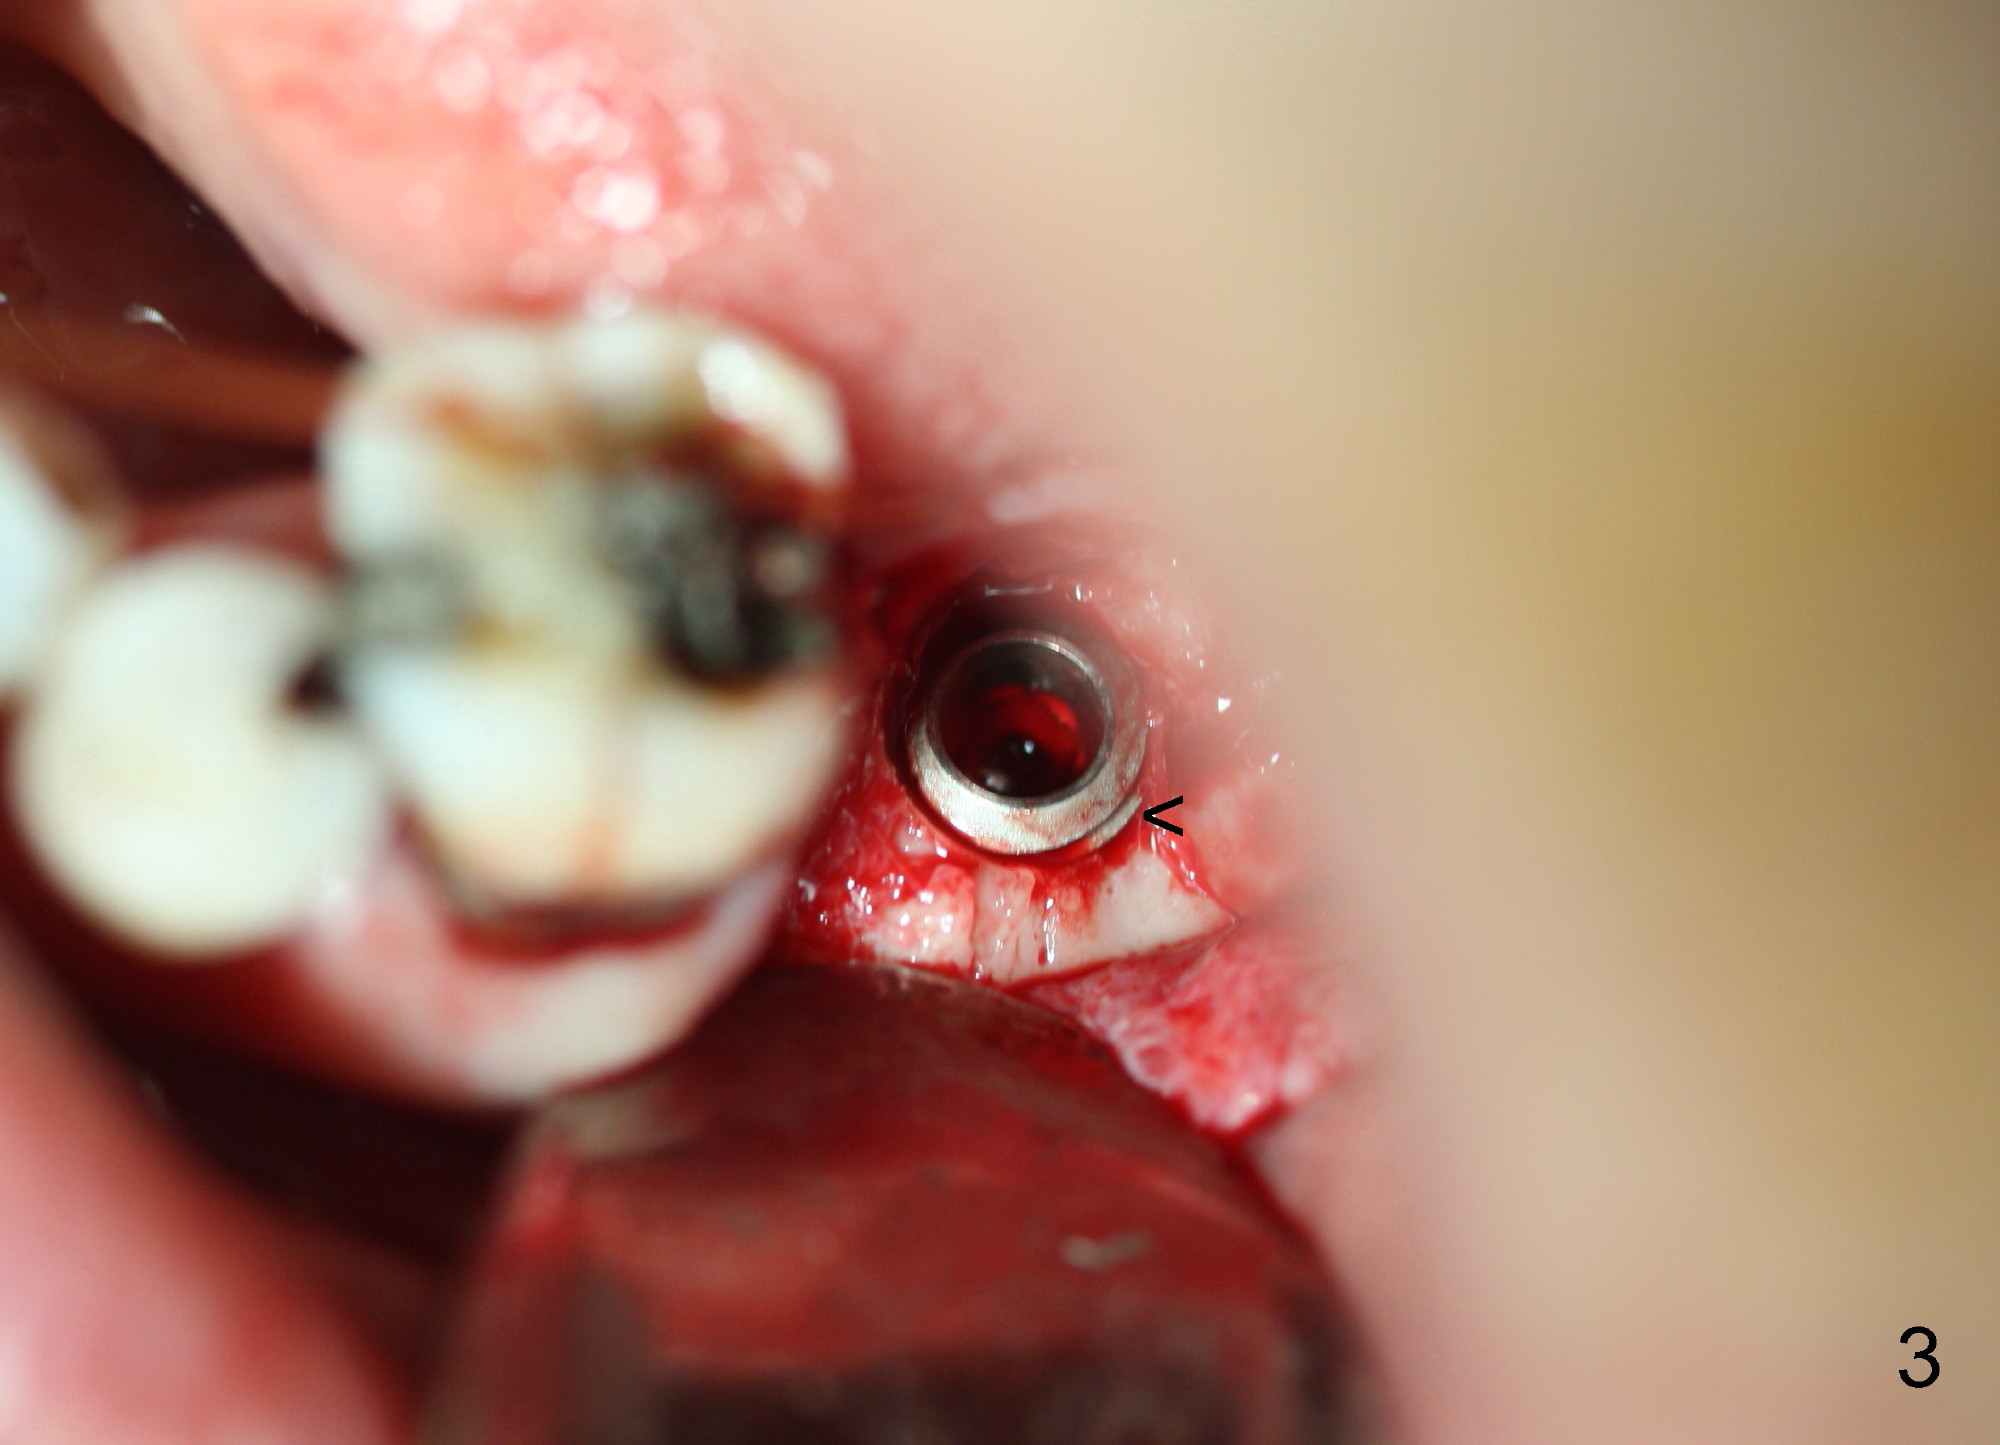

The 69-year-old male is a dental phobic with poor dentition. He wants to an implant at the site of #18 first and refuses to have the tooth #11 (with asymptomatic apical abscess) extracted. To reduce chance of post-implant infection, the implant is placed in a two stage manner. The distal amalgam overhang of the tooth #19 is removed by Piezo scaler (Fig.1). An incision is made. After a 2 mm pilot drill, a parallel pin is inserted; it appears that the coronal end of the trajectory should be leaned mesially (Fig.1 arrow). Since the ridge is wide, an extra wide implant is placed (Fig.2 I: 5.9x10 mm with insertion torque >50 Ncm) with one distal thread exposed (Fig.2,3 <). The disto-occlusal caries of the tooth #20 (Fig.1,4 *) is going to be excavated.